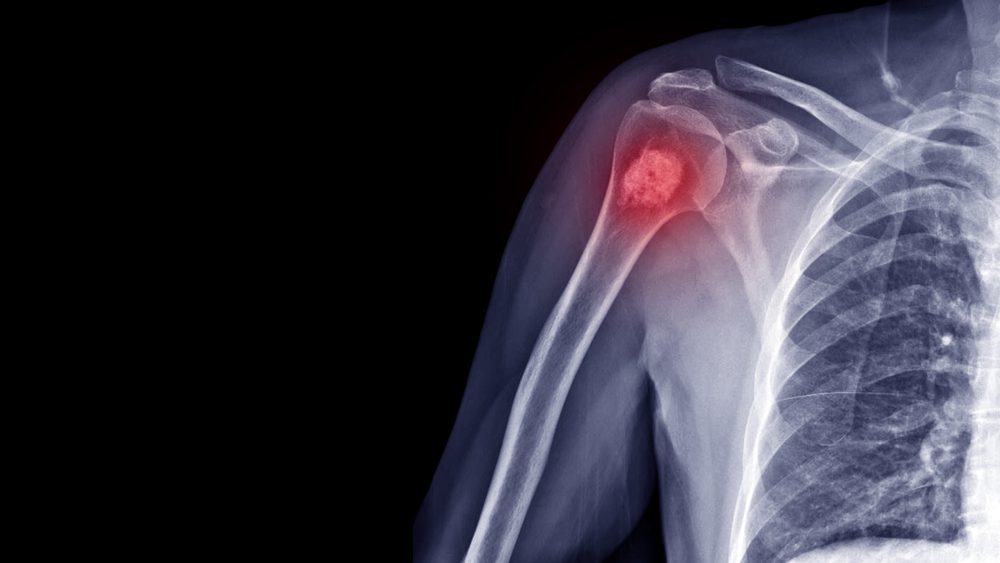

Bone metastasis can appear in any bone but is more common in the upper leg bone (femur), the ribs, the skull, the hip bone, or the upper arm bone. When you have bone cancer, your body is either making too much bone or breaking it down too fast. Both of these sudden changes can make your bones break more easily.